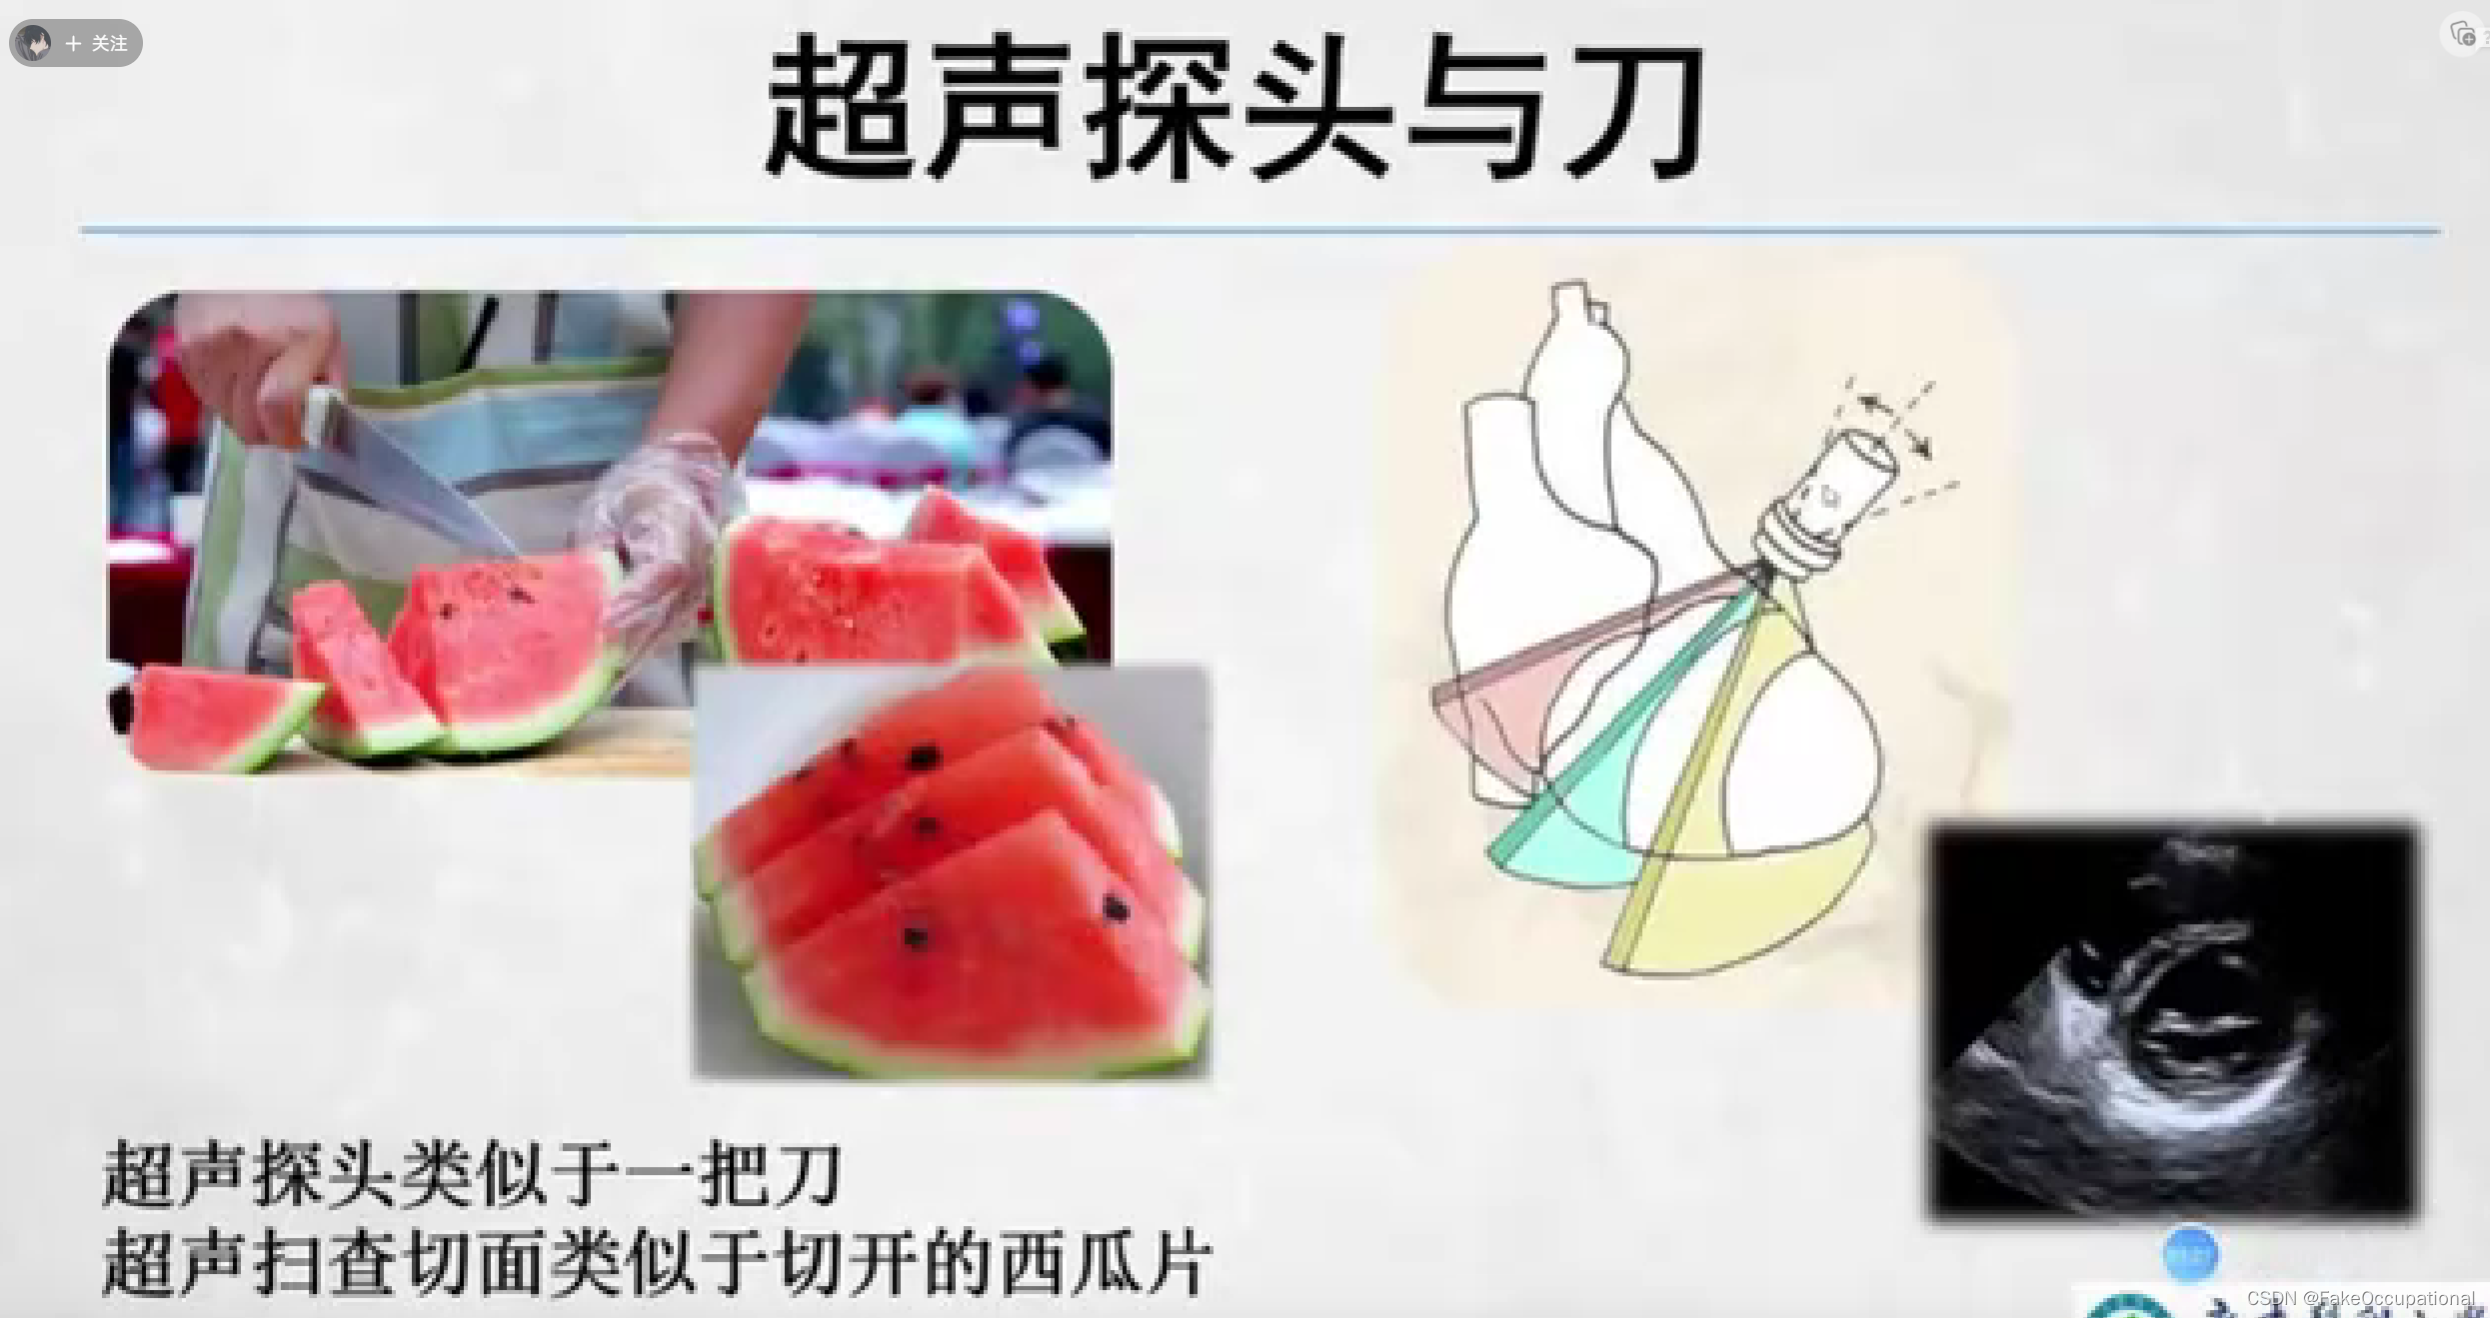

- 探头上是有方位标记点的,显示器中方位点在左侧。标准方向放置后,患者的右侧应该出现在显示器的左侧。探头一侧的探头方向标记应面向患者的右侧(如果探头纵向定向,则朝向头侧),并且超声监视器上的标记点位于超声监视器的左上角。

- 图中前后指的是深度